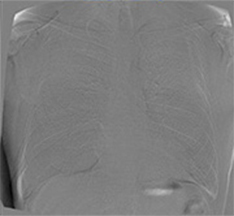

胸部経時差分処理

Temporal Subtraction処理

Temporal Subtraction処理は、独自のアルゴリズム補正をもとに、胸部画像の現在と過去の差分画像を生成する画像処理技術です。

そこで、現在と過去の差分画像を生成し「変化の有無」を可視化することで、診断精度の向上と時間短縮が期待でき、胸部読影を強力にサポートします。

◆変化が可視化され、新規病変の認識がしやすくなる。

◆肺門部や心臓裏の見落としやすい部位の病変が見つけやすくなる。

◆過去画像と現在画像の比較により経時的変化が画像化され、経過観察が容易になる。

経時変化の差がドーナツ形状として現れることで、一見「変化なし」としがちな病変の大きさ変化が認識可能です。

肺門部裏は見落としやすく重要な読影ポイントですが、経時差分画像により一目で変化が確認出来ます。

左肺尖部に濃度の上昇がありますが、通常画像では淡い変化の為、直ぐに気づきません。読影が難しい肺尖部の鎖骨裏などでも経時差分画像で即座に変化を確認できます。